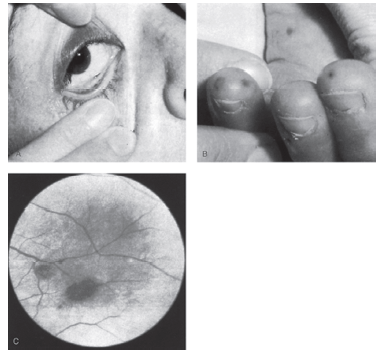

Os fenômenos retratados abaixo são manifestações características do seguinte quadro infeccioso:

Provas